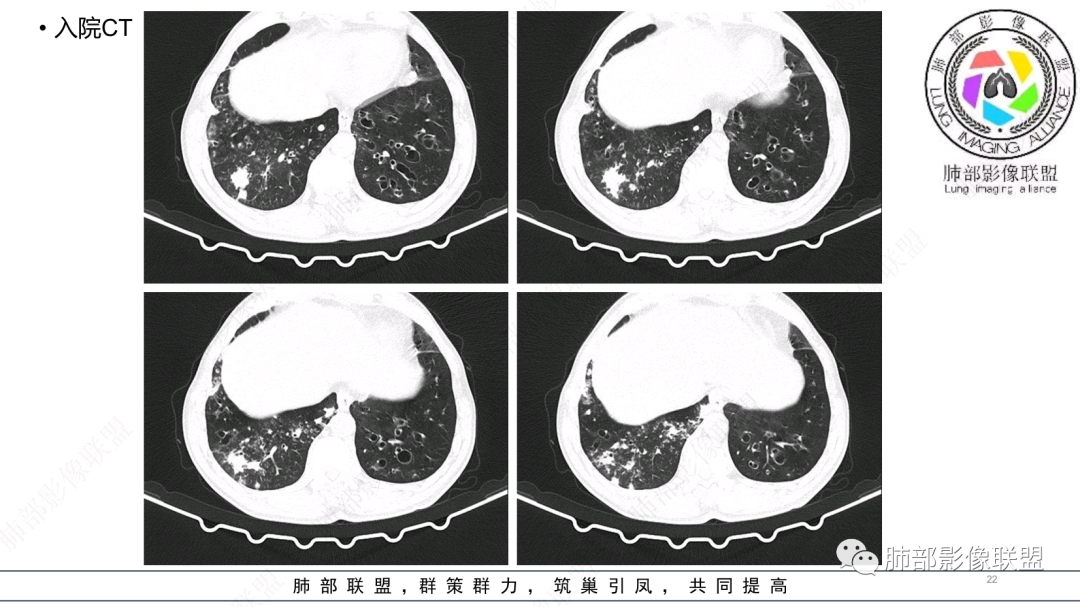

中老年男性,发病一周,发热,炎症指标明显增高,双肺支气管扩张基础,双肺可见多发结节、斑片状、团块状密度增高,边缘尚清。病灶分布与支气管关系密切,考虑支扩合并感染,铜绿,NTM、奴卡、曲霉等,环卫工人,可能接触腐败物较多,考虑曲霉可能大,鉴别奴卡。

男性,56岁,清洁工,临床表现咳嗽咳痰发热。胸部影像:两肺散在斑片、结节及实变影,大部分沿气道分布,以下肺为著并伴发多发支气管扩张及囊腔影,实验室检查白细胞增高,考虑感染性病变,曲霉、铜绿及NTM。

56岁,工作性质:环卫工人。主诉:咳、痰、喘、发病一周。急性起病(或者慢病+AE),呼吸道感染症状。化验指标白细胞、中性、CRP明显升高。影像学显示多灶性,有柱状支扩,囊状支扩等结构肺病,责任细菌主要考虑铜绿假单胞菌,不排除合并其他细菌以阴杆为主;存在树芽影,发热,炎症沿支气管束分布,是否合并TB?真菌?;树芽伴发热支原体感染也要需要考虑进去;全肺多灶性炎症,部分病灶周围有晕,右上叶疑似反晕,内部疑似有丝,右下肺考虑存在粘液栓,加之环卫工工作性质,考虑霉菌,主要考虑曲霉。

两肺支扩,两肺沿支气管分布多发结节、树芽及团块,边缘模糊,部分支气管管壁增厚,考虑气道侵袭性曲霉菌,鉴别铜绿、奴卡、结核。

支气管壁增厚,晕征明显,病灶沿着支气管纵向分布,结合患者职业,考虑气道侵袭性曲霉。

多发结节,部分结节边缘清楚,部分边缘模糊,支扩合并肉芽肿性炎,奴卡菌与曲霉之间选择。

CT:双肺延支气管血管束分布斑片状、团块状、树芽状密度增高影,部分边界模糊,支气管扩张、部分管壁增厚。考虑气道吸入细菌性感染,铜绿假单孢?